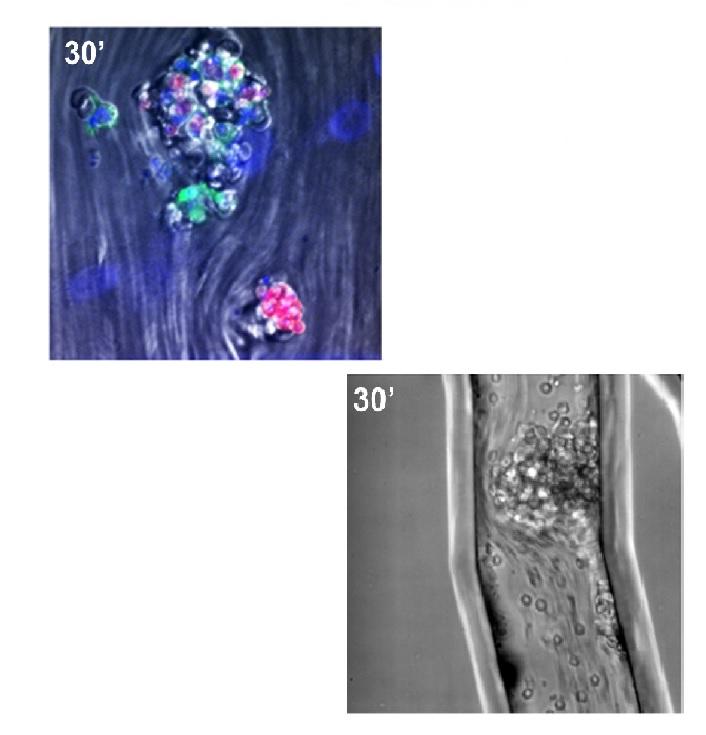

E. K.S. Lee, M. R. Gillrie, L. Li, J. W. Arnason, J. H. Kim, L. Babes, Y. Lou, A. Sanati-Nezhad, S. K. Kyei, M. M. Kelly, C. H. Mody, M. Ho, B. G. Yipp, "Leukotriene B4-mediated neutrophil recruitment causes pulmonary capillaritis during lethal fungal sepsis", Cell Host and Microbe, 23 (1), 121-133. e4, 2017.